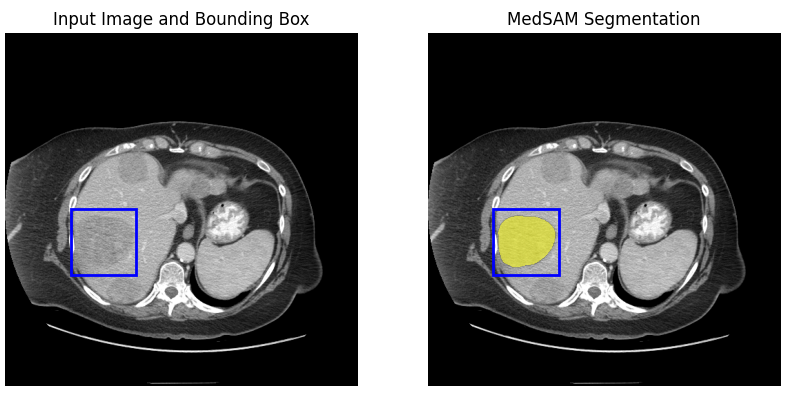

fig, ax = plt.subplots(1, 2, figsize=(10, 5))

ax[0].imshow(np.array(raw_image))

show_box(input_boxes, ax[0])

ax[0].set_title("Input Image and Bounding Box")

ax[0].axis("off")

ax[1].imshow(np.array(raw_image))

show_mask(mask=probs[0] > 0.5, ax=ax[1], random_color=False)

show_box(input_boxes, ax[1])

ax[1].set_title("MedSAM Segmentation")

ax[1].axis("off")